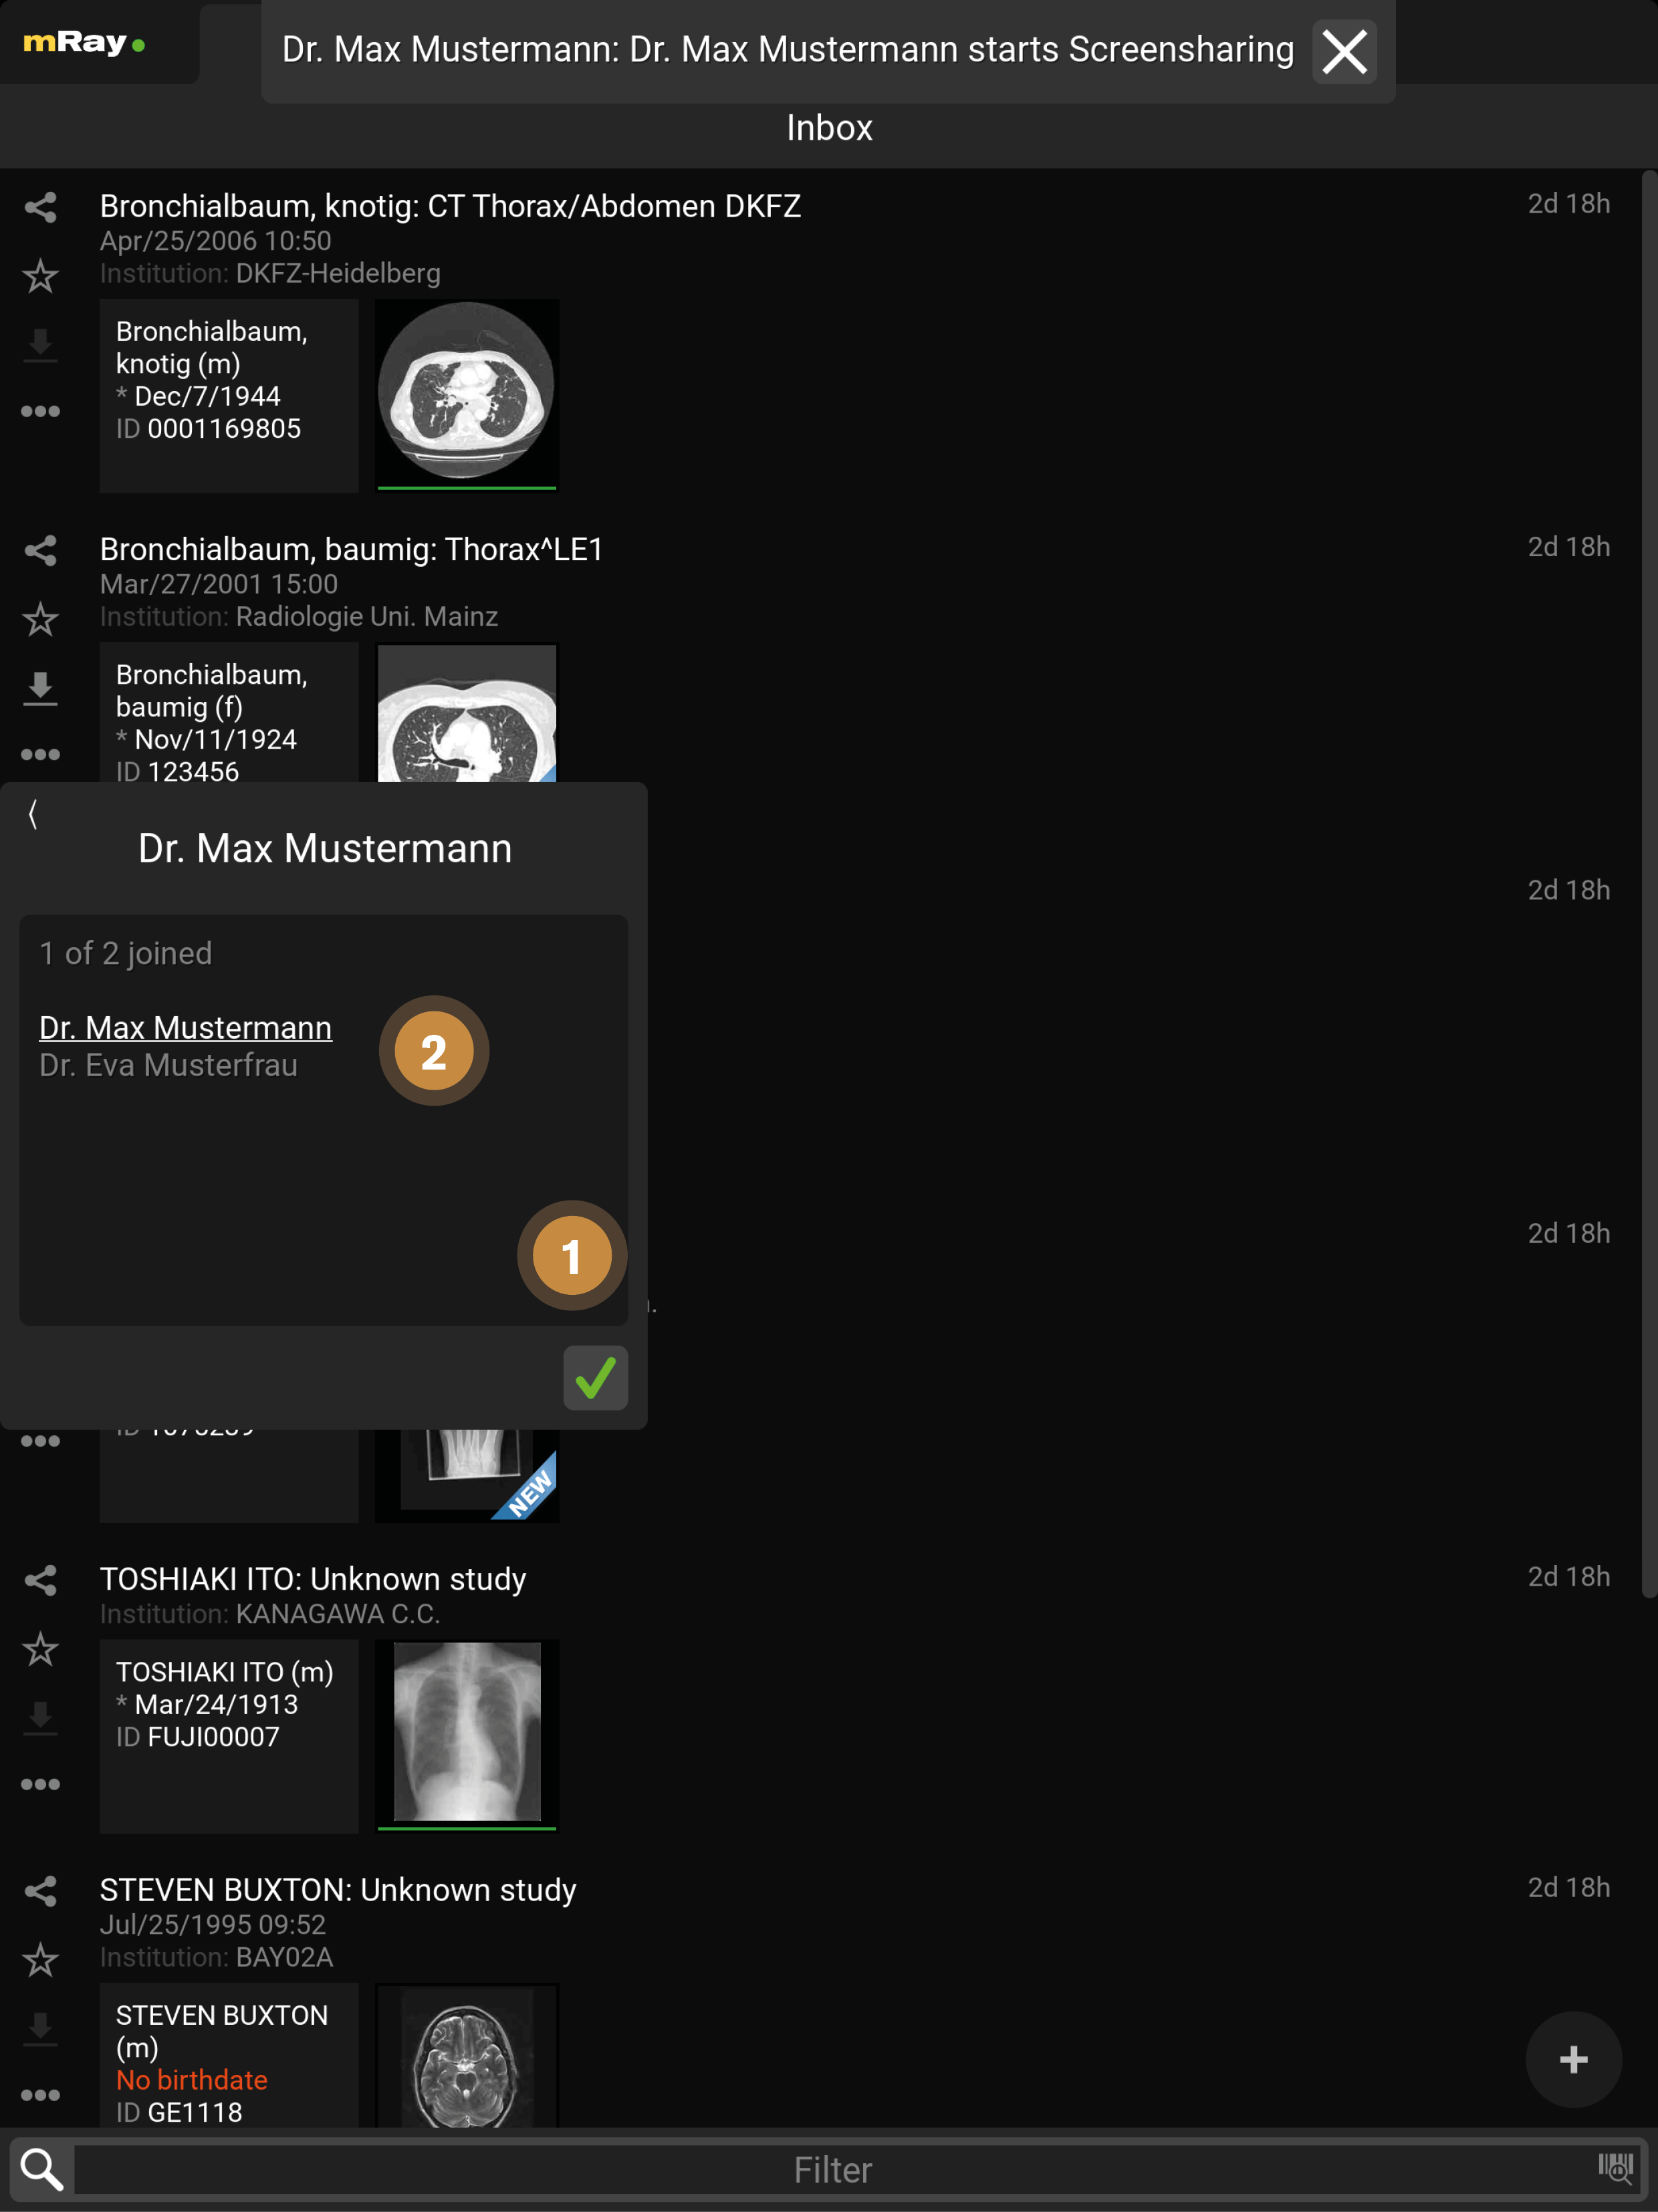

9.1. Inbox

Nach dem Einloggen öffnet sich die „Inbox“ (Inbox). Über diese können Sie den gewünschten DICOM Datensatz selektieren, der Ihnen über den eingestellten Server zur Verfügung gestellt wurde. Sie sehen hier also alle am mRay-Server vorliegenden Daten, auf die Sie Zugriffsrechte haben.

-

Durch Anklicken des mRay-Logos öffnet sich das Hauptmenü (siehe Hauptmenü).

-

Ein grünes Symbol zeigt an, dass Sie mit dem Server verbunden sind. Bei einem roten Symbol können Sie mit den lokal gespeicherten Daten arbeiten, aber erhalten natürlich keine neuen Datensätze.

-

Wechseln zur Inbox oder zum Anfang der Liste, wenn dies der aktive Reiter ist.

-

Wechseln zum Messaging (nur vorhanden, falls diese Funktion in Ihrem System aktiviert wurde)

-

Wechseln zur Suche. Hier können Sie den gesamten für Sie verfügbaren Datenbestand durchsuchen. Sie haben außerdem die Möglichkeit Suchanfragen an ein PACS zu stellen (falls eingerichtet).

-

Wechseln zu den Favoriten: Favoriten können Sie mit Hilfe der Stern-Symbole (Punkt 8) markieren. Favoriten funktionieren als eine Art "Lesezeichen" und werden vom automatischen Speichermanagement der Anwendung als Letztes gelöscht (d. h. nur wenn das Löschen notwendig ist aufgrund der Einstellungen zur Datenvorhaltung oder aufgrund eines niedrigen Speicherplatzes auf dem Gerät).

-

Wechseln zur Fotodokumentation

-

Klicken Sie hier, um zur Bildansicht (Viewer) mit den zuvor geöffneten Bildern zurückzukehren.

-

Hier können Sie schnell und einfach ganze Studien teilen

, als Favorit markieren

, als Favorit markieren  bzw. auf ihr Gerät exportieren

bzw. auf ihr Gerät exportieren  .

Weitere Aktionen für die ganze Studie lassen sich über das Kontextmenü

.

Weitere Aktionen für die ganze Studie lassen sich über das Kontextmenü  ausführen.

ausführen. -

Hier werden Informationen bzw. auch fehlende Informationen und Metadaten zum Patient angezeigt.

-

Hier sehen Sie eine Übersicht der Serien innerhalb der Studie. Durch Anklicken einer Studie kommen Sie in die Serienauswahl (siehe Serienauswahl). Der grüne Balken unter jedem Vorschaubild zeigt an ob der Datensatz lokal auf Ihr Gerät heruntergeladen und offline verfügbar ist.

-

Hier erscheint, wann der Datensatz in der Inbox ankam (d. h. durch Schicken aus dem PACS bzw. Suche im Datenbestand). mRay kann so konfiguriert werden, dass Datensätze automatisch nach 'X' Stunden wieder vom Gerät gelöscht werden (Standard: Nach 8 Stunden).

-

Hier können mehrere Studien zum Teilen ausgewählt werden.

-

Hier können Sie die Inbox nach einer Texteingabe filtern. Bitte beachten: Hiermit starten Sie keine PACS-Suchanfrage! Bitte benutzen Sie dazu Punkt 3 Suche. Beachten Sie auch die Hinweise zu Sonderzeichen im Kapitel „Bekannte Probleme“.

-

Fotofunktion aufrufen: Siehe Abschnitt Fotodokumentation zur näheren Erläuterung.

-

Datei-Upload: Laden Sie eigene DICOM Daten auf Ihren Server. Nur verfügbar wenn vom Server unterstützt.

14. Screensharing

Das Screensharing ermöglicht es, Ihren Bildschirm mit anderen zu teilen. Nach der Betätigung des Buttons (siehe Chat) startet das Screensharing und es öffnet sich das bereits von Ihnen geöffnete Bild (siehe Chat) oder Sie werden an die Inbox weitergeleitet, wenn noch kein Bild geöffnet wurde. Das Screensharing kann mit einer oder mehreren Personen (siehe Screensharing in Gruppen), in Form einer Gruppe, gestartet werden.

In einem Chat ist derjenige Administrator, der das Screensharing startet. In einer Gruppe wird der Administrator zuvor festgelegt (siehe Screensharing in Gruppen).

Die Ansicht stellt folgende Funktionen zur Verfügung:

-

Derjenige der das Screensharing gestartet hat wird weiß unterstrichen, die aktiven Teilnehmer werden weiß und die inaktiven Teilnehmer der Gruppe grau dargestellt.

-

Mit dem "Mikrofon"-Button kann ein Teilnehmer die Sprachfunktion aktivieren und beenden (durchgestrichen). Der sprechende Teilnehmer wird gelb dargestellt.

-

Durch den X-Button kann das Screensharing verlassen werden.

-

Nur der Administrator kann während des Screensharings Werkzeuge anwenden.

-

Hier kann das Fenster minimiert werden.

Die Ansicht stellt folgende Funktionen zur Verfügung:

-

Durch den "grüner Haken"-Button kann der Teilnehmer dem Screensharing beitreten.

-

Der Administrator wird weiß unterstrichen, die aktiven Teilnehmer werden weiß und die inaktiven Teilnehmer der Gruppe grau dargestellt.